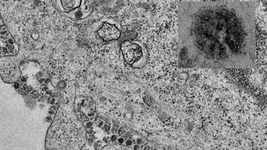

Вот вроде реальные снимки заражённых коронавирусом клеток.

Я говорил в принципе о цвете.. В реале , если оптика для таких разрешений вблизи дифракционного предела, то она очень короткофокусная(ну, типа, объектив практически соприкасается с наблюдаемым объектом), поэтому те другие вирусы на заднем плане - это точно картинка для красоты. Реально в таком микроскопе всё, что за фокусом будет размыто- то есть не будет ничего видно ... А здесь - прямо такая художественная глубина резкости... Так в реале ничего не выглядит.